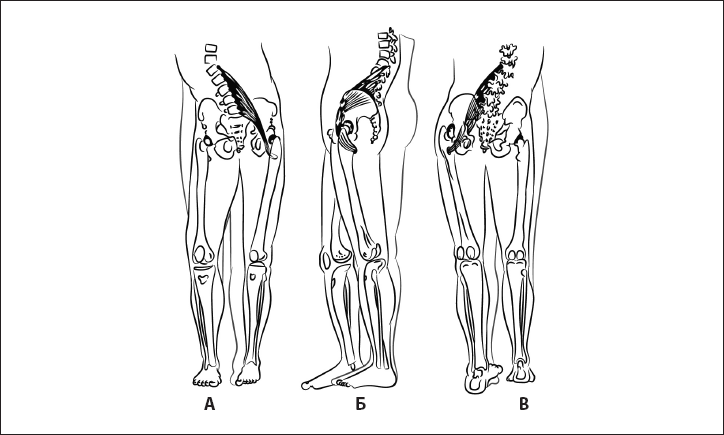

Рис. 32. Укорочение пояснично-подвздошной мышцы. А – вид спереди, Б – вид сбоку, В – вид сзади.

Биомеханика. Коленный сустав в разогнутом состоянии обеспечивает стабилизацию ноги при опоре на нее. Визуальные критерии – разгибание коленного сустава.

Ошибка. Сгибание коленного сустава и опора на полусогнутый сустав. Причина – в гипотонии четырехглавой мышцы бедра и укорочении пояснично-подвздошной мышцы, разгибателей бедра (рис. 32). В результате нарушается стабильность таза и коленного сустава, происходит перегрузка менисков коленного сустава в зависимости от локализации компенсаторно-перегруженной мышцы.

Рис. 39. Гипотония пояснично-подвздошной мышцы. А – вид спереди, Б – вид сбоку, В – вид сзади.